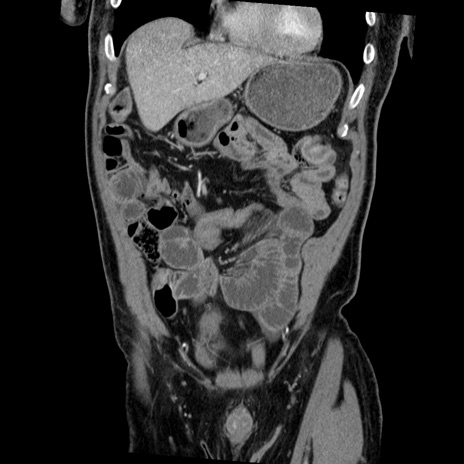

症例22(冠状断像)

【症例】50歳代男性

【主訴】腹痛

【現病歴】AVMからの被殻出血のため回復期リハ病棟入院中。 本日午後3時頃急に下腹部痛が出現した。

【既往歴】AVM、被殻出血、虫垂炎、高血圧

【身体所見】意識晴明、左半身不全麻痺、会話の理解は良好、36.5°C、腹部:膨隆、全体に板状硬、下腹部正中に圧痛点あり、反跳痛-、筋性防御不明、右下腹部にope scar

【データ】WBC 9400、CRP 0.06

横断像